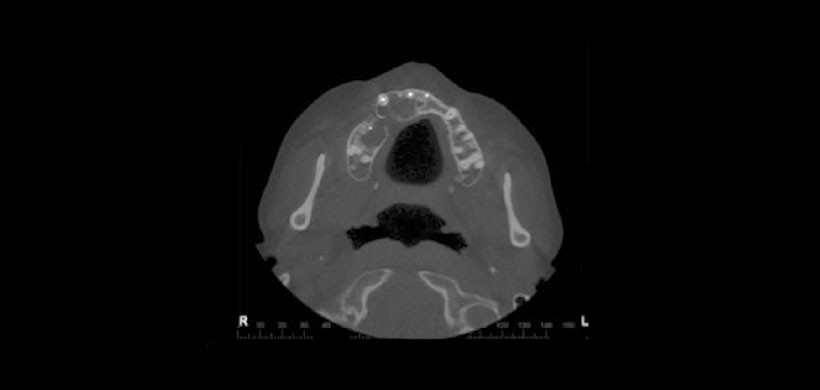

Figura 7: Tomografía cone beam (CBCT) 6 meses posterior a la infiltración. Corte axial que muestra la neoformación ósea (septum)